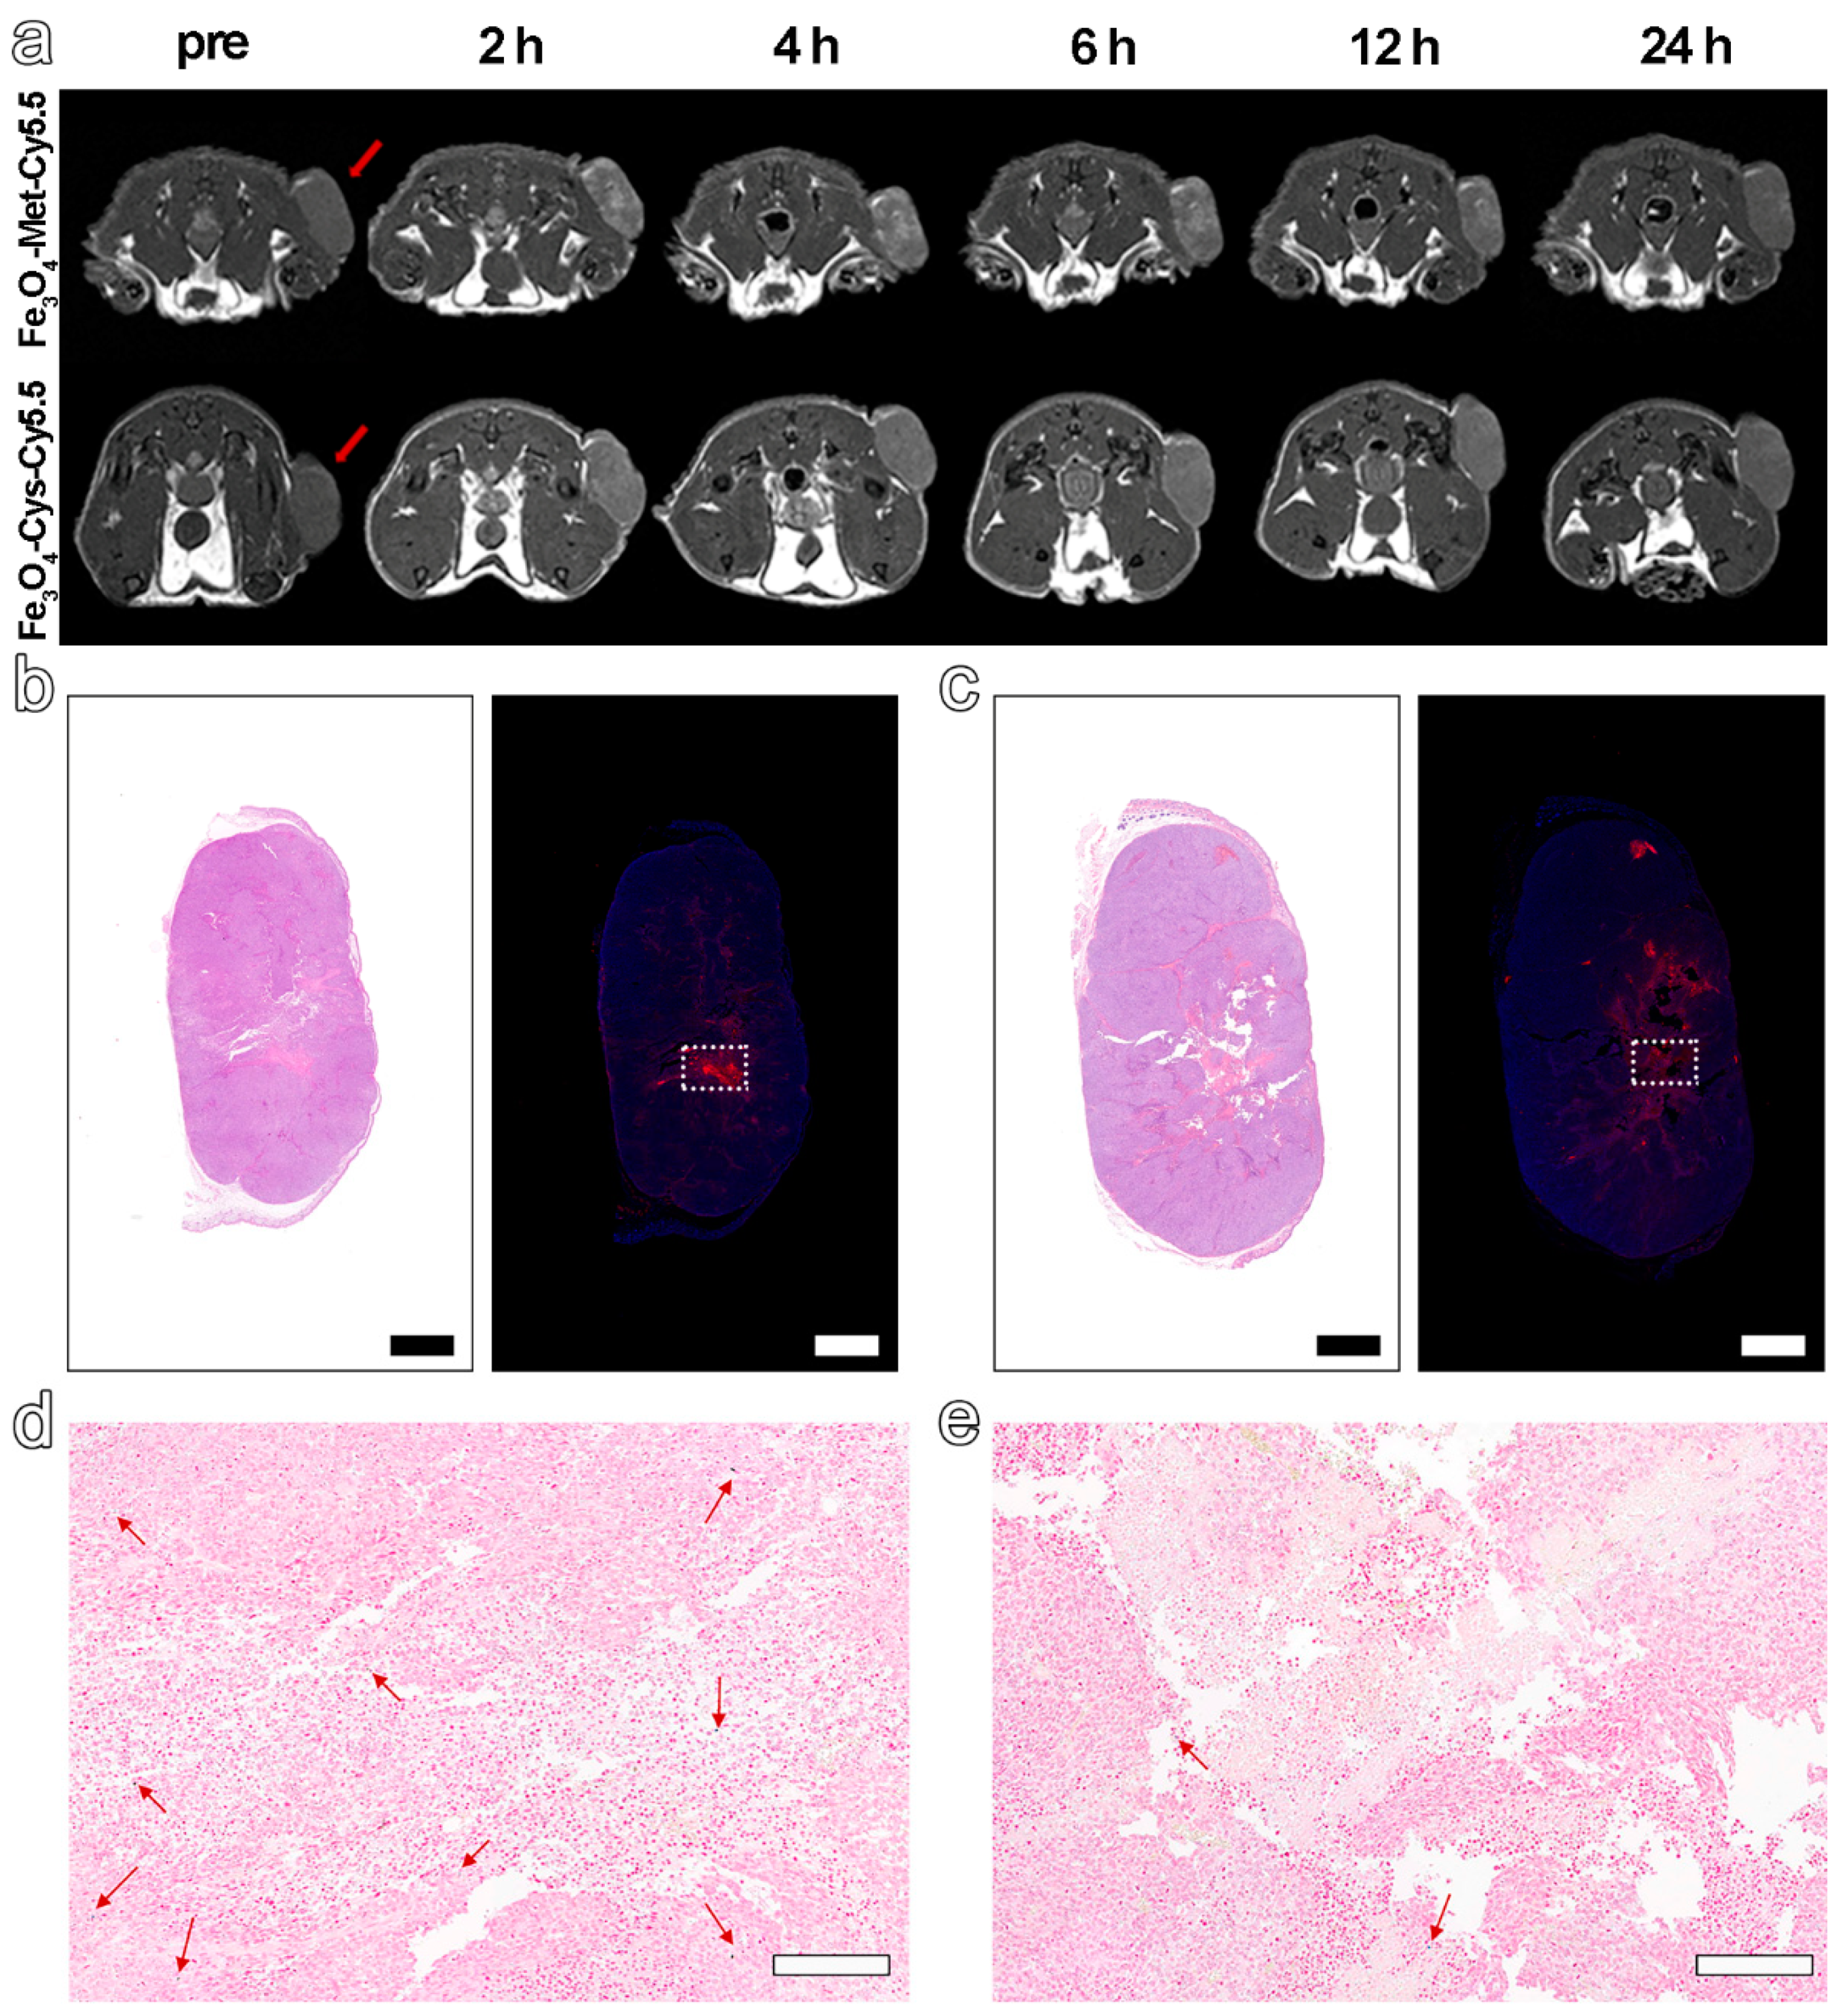

Based on the excellent hypoxia sensitivity in vitro, the nanoprobes were further intravenously injected into MCF-7 tumor-bearing mice (5.6 mg Fe kg−1 bodyweight) to explore the ability to detect hypoxia in vivo via MRI. The T1-weighted MR images at different time points before (pre) and post-injection (2 h, 4 h, 6 h, 12 h, 24 h) were collected by 3 T MRI apparatus. The results in Figure 4a displayed an obvious brightening trend in the signal arising from the tumor site for both groups and up to 6 h post-injection. However, from 6 to 24 h after injection, a decreasing signal tendency was identified for both groups. Furthermore, the normalized ratio of signal intensity arising from the tumor site to that of normal muscle (T/N) in Figure 4a and Figure S7 clearly exhibited that Fe3O4-Met-Cy5.5 could provide a higher contrast than that of Fe3O4-Cys-Cy5.5 (1.39 vs. 1.18 at 6 h post-injection). Anyway, the trend of the MRI signals in the two groups had statistically significant differences at 2, 4, 6, and 12 h post-injection (Figure S8a). Based on the above results, the ability of Fe3O4-Met-Cy5.5 and Fe3O4-Cys-Cy5.5 to target the tumors through the EPR effect can presumably be considered similar, due to their similar sizes and surface modifications. Therefore, this higher tumor contrast was assumed to originate from the hypoxic condition of the tumor, which might lie in the specific accumulation of metronidazole moieties. This conjecture is reasonable as the central area of the tumor site in Figure 4a, which preferred a hypoxic state, due to the limited oxygen supply capacity, and was visibly brighter than the surrounding region of the tumor treated with Fe3O4-Met-Cy5.5. To verify this assumption, the tumors were harvested and subjected to H&E and immunofluorescence staining of the HIF-1α antibody. As illustrated in Figure 4b,c, areas of tumor necrosis in H&E staining and hypoxic regions in HIF-1α staining were identified for both groups. More importantly, the distribution of the red fluorescence of HIF-1α, given in Figure 4b, was generally consistent with the brightening area of Fe3O4-Met-Cy5.5-treated group, verifying that our previous assumption was valid. In addition, Prussian blue staining of the hypoxic regions from the adjacent slices showed that both nanoprobes still had retention in the tumor regions after injection for 24 h (Figure 4d,e).

Figure 4.

(a) T1-weighted MRI of tumor-bearing mice within 24 h, before and after injection with Fe3O4-Met-Cy5.5 or Fe3O4-Cys-Cy5.5. H&E staining (left) and immunofluorescence staining (right) for tumors of mice injected with Fe3O4-Met-Cy5.5 (b) or Fe3O4-Cys-Cy5.5 (c) (scale bars represent 1000 μm). Prussian blue staining of hypoxic area (dashed area on immunofluorescence staining images) in the tumors of mice treated with Fe3O4-Met-Cy5.5 (d) or Fe3O4-Cys-Cy5.5 (e) (scale bars represent 200 μm).